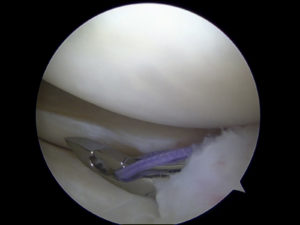

Meniscus Tear Repair

The meniscus is a band of cartilage that provides cushioning and stability for the knee joint. When this band becomes torn, it can cause immense pain and limit your ability to move properly. The most common reasons for this injury are sudden twisting and overuse. Treatment for a meniscus tear often includes rest, physical therapy, anti-inflammatory drugs, and surgery. Here's what you need to know about recovery from this injury and where you can go for the treatment of meniscus tears in [Read More]

Each knee has two moon-shaped sections of protective cartilage, and each section is called a meniscus. Together, the menisci provide essential cushioning between the top of the shinbone (large lower leg bone) and the bottom of the thighbone (upper leg bone) so that the bones do not rub against one another during movement. The menisci can tear during strong twisting, high-impact landing, or pivoting motions of the knee. Meniscus tears are a common injury while playing sports such as football, [Read More]